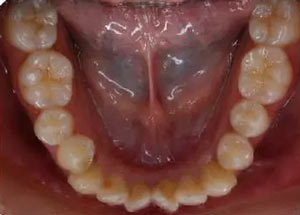

下牙弓:卵圓形,下前牙區(qū)擁擠

上牙弓擁擠度9mm;下牙弓擁擠度7mm;

Spee曲線1.5mm;前牙開(kāi)合3mm;深覆蓋4mm

橫向:上下牙弓寬度不匹配,下牙弓寬度較上牙弓大,左側(cè)自第一磨牙開(kāi)始至側(cè)切牙均為反合。上牙列中線左偏,下牙列中線右偏。